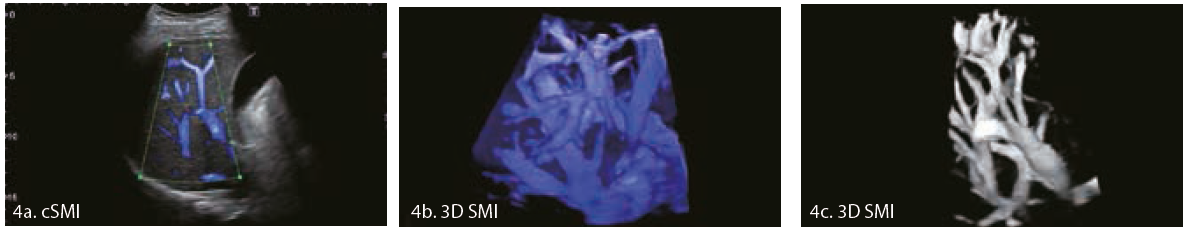

У      нашому      закладі      нагляд      за      пухлинами розпочинають, якщо виявлені такі погані прогностичні фактори, як вузлові метастази, лімфоваскулярна інвазія, мезоапендикулярна інвазія або змішана патологія. Цю пацієнтку обстежили за допомогою ультразвуку, підозрілих ділянок не виявлено. SMI було додано до ультразвукового дослідження (Малюнок 4a-4c) для покращення чутливості виявлення ізоехогенних метастазів у печінку. Хоча чутливість ультразвуку при виявленні метастазів у печінку менша, ніж КТ з контрастуванням, іонізуюче випромінювання та поглинання контрасту при КТ є проблемою у молодих пацієнтів, яким може знадобитися додаткове спостереження. Метастази  нейроендокринної пухлини в печінку можуть бути гіпер- або гіпоехогенними в навколишній тканині печінки, але майже завжди гіперваскулярні.

Малюнок 4 Хлопчик-підліток з карциноїдною пухлиною в анамнезі.

Ультразвукове дослідження з 3D SMI покращує нашу діагностичну впевненість без необхідності вводити внутрішньовенні контрастні речовини або піддавати пацієнтів впливу іонізуючого випромінювання. Розумний 3D SMI дає змогу швидко отримати дані з великих ділянок тканини, наприклад печінки, для відображення тривимірних деталей  судин  з  високою  просторовою роздільною здатністю.